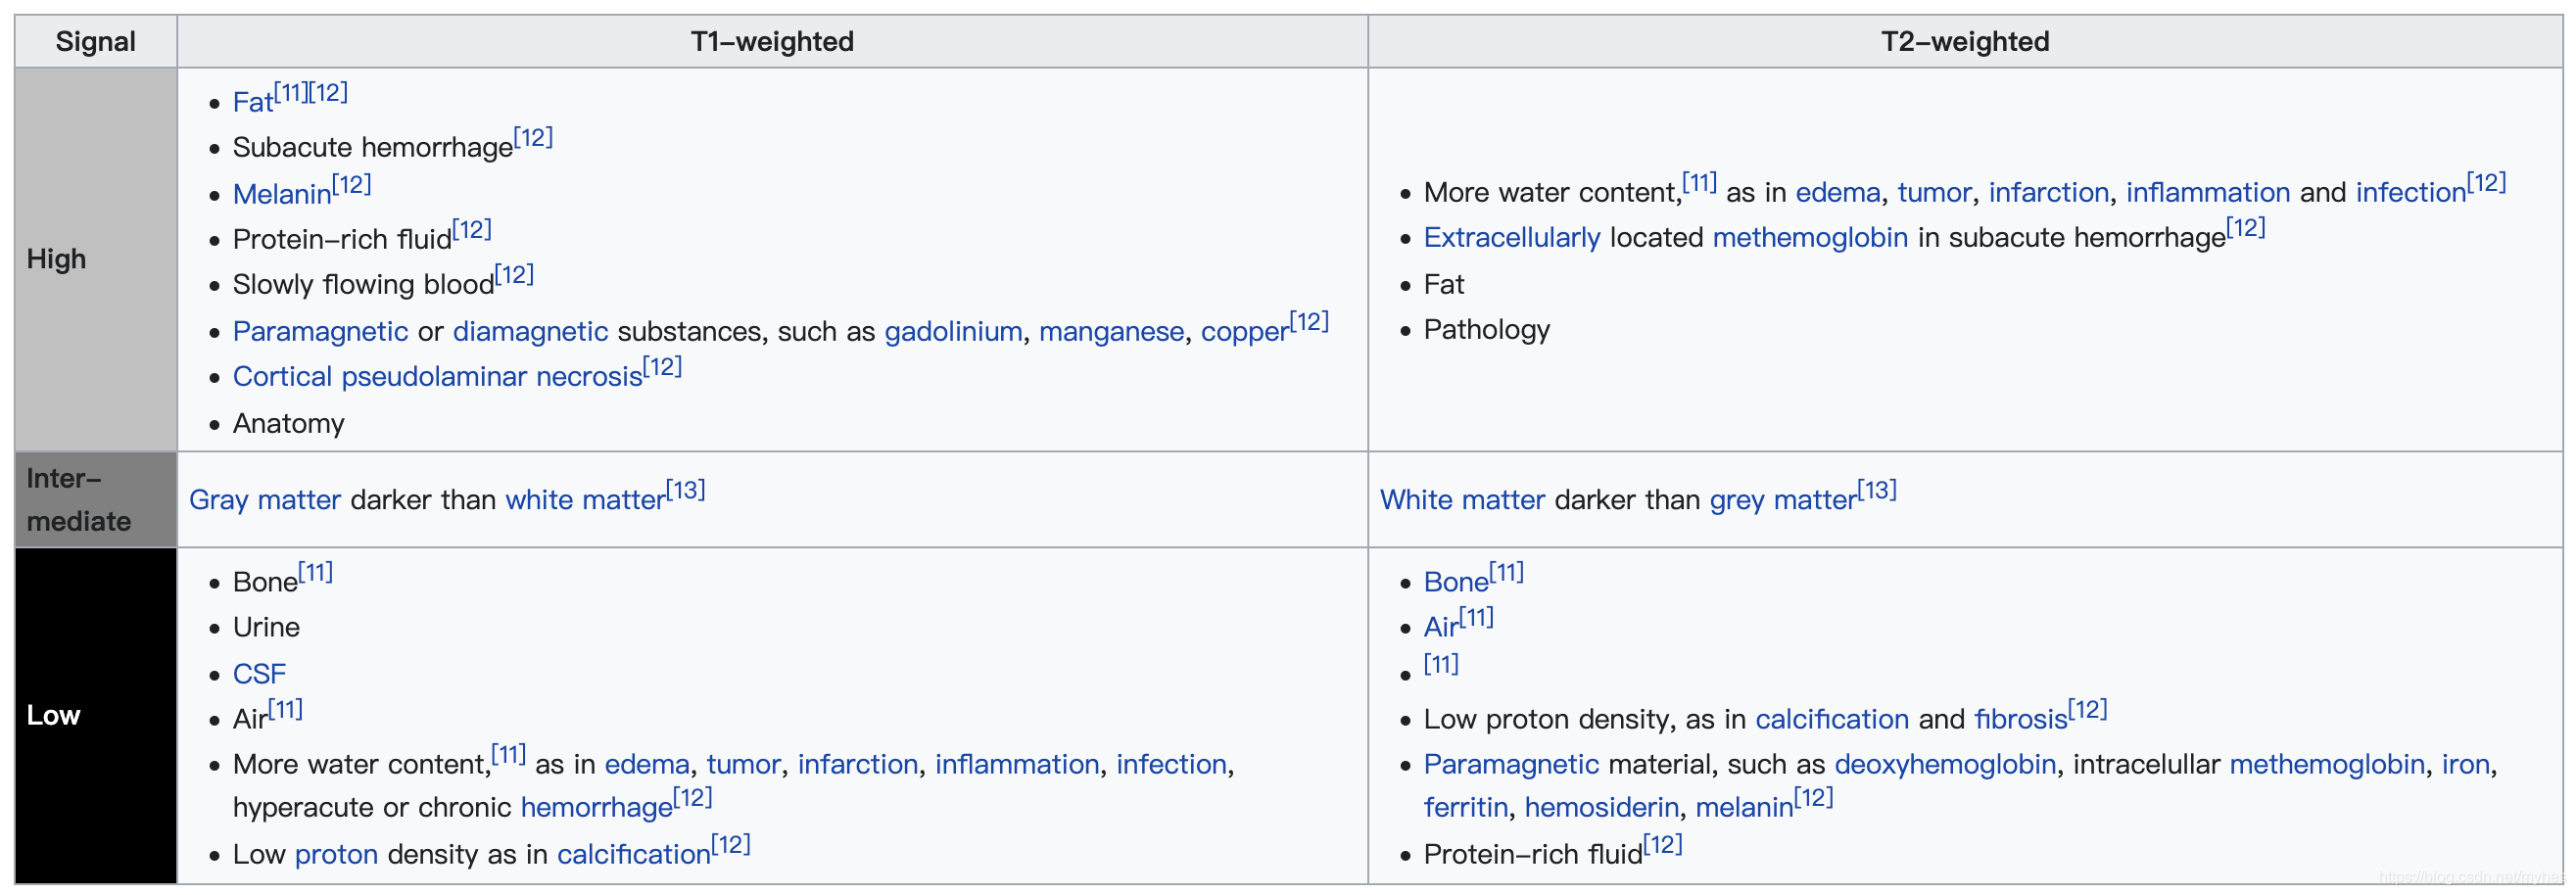

MRI通过对静磁场中的人体施加某种特定频率的射频脉冲,使人体中的氢质子受到激励而发生磁共振现象。停止脉冲后,质子在弛豫过程中产生MR信号。通过对MR信号的接收、空间编码和图像重建等处理过程,即产生MR信号。

核磁共振成像原理:原子核带有正电,许多元素的原子核,如1H、19FT和31P等进行自旋运动。通常情况下,原子核自旋轴的排列是无规律的,但将其置于外加磁场中时,核自旋空间取向从无序向有序过渡。自旋的核同时也以自旋轴和外加磁场的向量方向的夹角绕外加磁场向量旋进,这种旋进叫做拉莫尔旋进,就像旋转的陀螺在地球的重力下的转动。自旋系统的磁化矢量由零逐渐增长,当系统达到平衡时,磁化强度达到稳定值。如果此时核自旋系统受到外界作用,如一定频率的射频激发原子核即可引起共振效应。这样,自旋核还要在射频方向上旋进,这种叠加的旋进状态叫做章动。在射频脉冲停止后,自旋系统已激化的原子核,不能维持这种状态,将回复到磁场中原来的排列状态,同时释放出微弱的能量,成为射电信号,把这许多信号检出,并使之能进行空间分辨,就得到运动中原子核分布图像。原子核从激化的状态回复到平衡排列状态的过程叫弛豫过程。它所需的时间叫弛豫时间。弛豫时间有两种即T1和T2,T1为自旋-点阵或纵向驰豫时间,T2为自旋-自旋或横向弛豫时间。